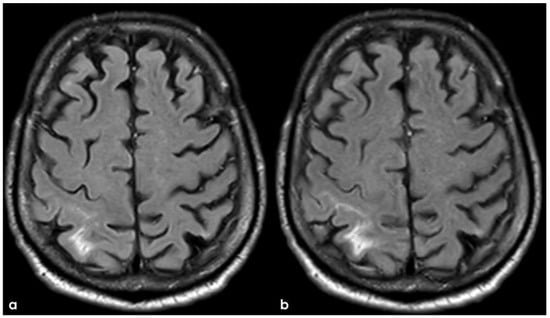

6. December 2017: Recurrent SAH